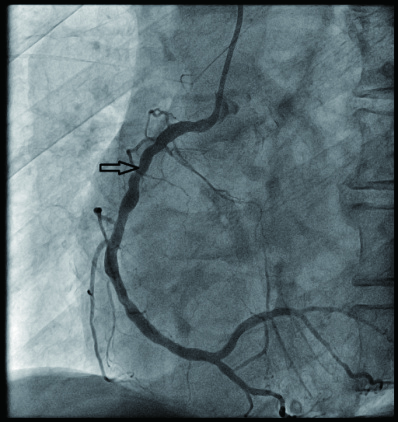

2 结果 本研究收集7例De winter综合征患者,6例进行了急诊冠脉造影,胸痛至球囊扩张平均时间为3.3 h,1例进行择期冠脉造影。其中,3例为前降支近段严重病变,1例为第一对角支闭塞,3例为前降支中段闭塞,2例合并多支血管病变,5例为单支血管病变,均行前降支支架植入术(表 4)。1周内行心脏彩超检查,4例出现室壁运动减弱,2例EF值小于50%,2例心脏形态结构未见异常,1例患者术后第2天因个人原因自动出院,未完善心脏彩超(表 5)。观察7例患者住院期间心电图演变情况,其中有3例在PCI术后出现前壁导联ST段抬高,4例未出现ST段抬高(表 5)。病例1住院期间出现室性心动过速,病例7患在急诊科就诊时发生呼吸心搏骤停,经抢救后送导管室行急诊冠脉造影。另外,所有患者经药物及介入治疗后,均症状缓解出院,院外长期服用阿司匹林100 mg/d+替格瑞洛90 mg/12 h+阿托伐他汀40 mg/瑞舒伐他汀20 mg等药物,出院1个月后电话随访,7例患者均无胸痛、气促发作及再住院,无死亡病例。

| 病例2 |

是 |

3(图 6~8) |

LAD近段 |

次全闭塞 |

2级 |

LAD近段植入支架1枚 |

| 注:LAD为左冠状动脉前降支; TIMI为心肌梗死溶栓治疗 |

表 5 7例患者的心电图演变及心脏彩超结果

| 编号 |

心电图是否演变为ST段抬高 |

心脏彩超 |

| 病例1 |

是(图 3~5) |

左心扩大,左室前间壁、前侧壁及心尖部运动减弱,EF 35% |

| 病例2 |

否 |

左室前间壁中下段运动稍减弱,EF 59% |